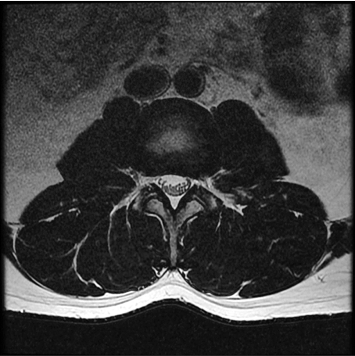

standard

384 x 256 (4 NEX)

3:02 minIAI (Innovative AI)

384 x 256 (2 NEX)

1:30 minReduced Scan Time

IAI는 AI Deep learning을 통해 기존 장비의 촬영 프로토콜을 최적화합니다.

기존 프로토콜 대비 촬영 시간을 50% 단축시키며, 이미지 퀄리티는 증가합니다.